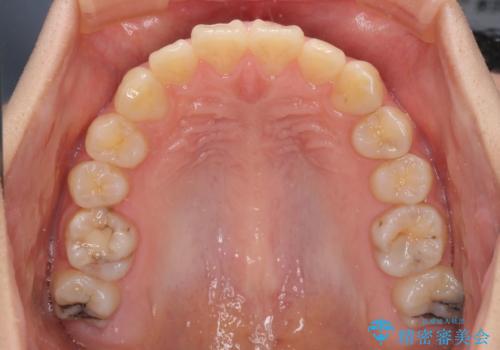

- 口元の突出感を気にして来院された患者様です。

上下左右の第一小臼歯4本を抜歯して口元を下げる治療計画としました。

非常に大きな虫歯のあった下顎大臼歯は、根管治療を行い、矯正治療後にオールセラミッククラウンにて補綴治療を行いました。